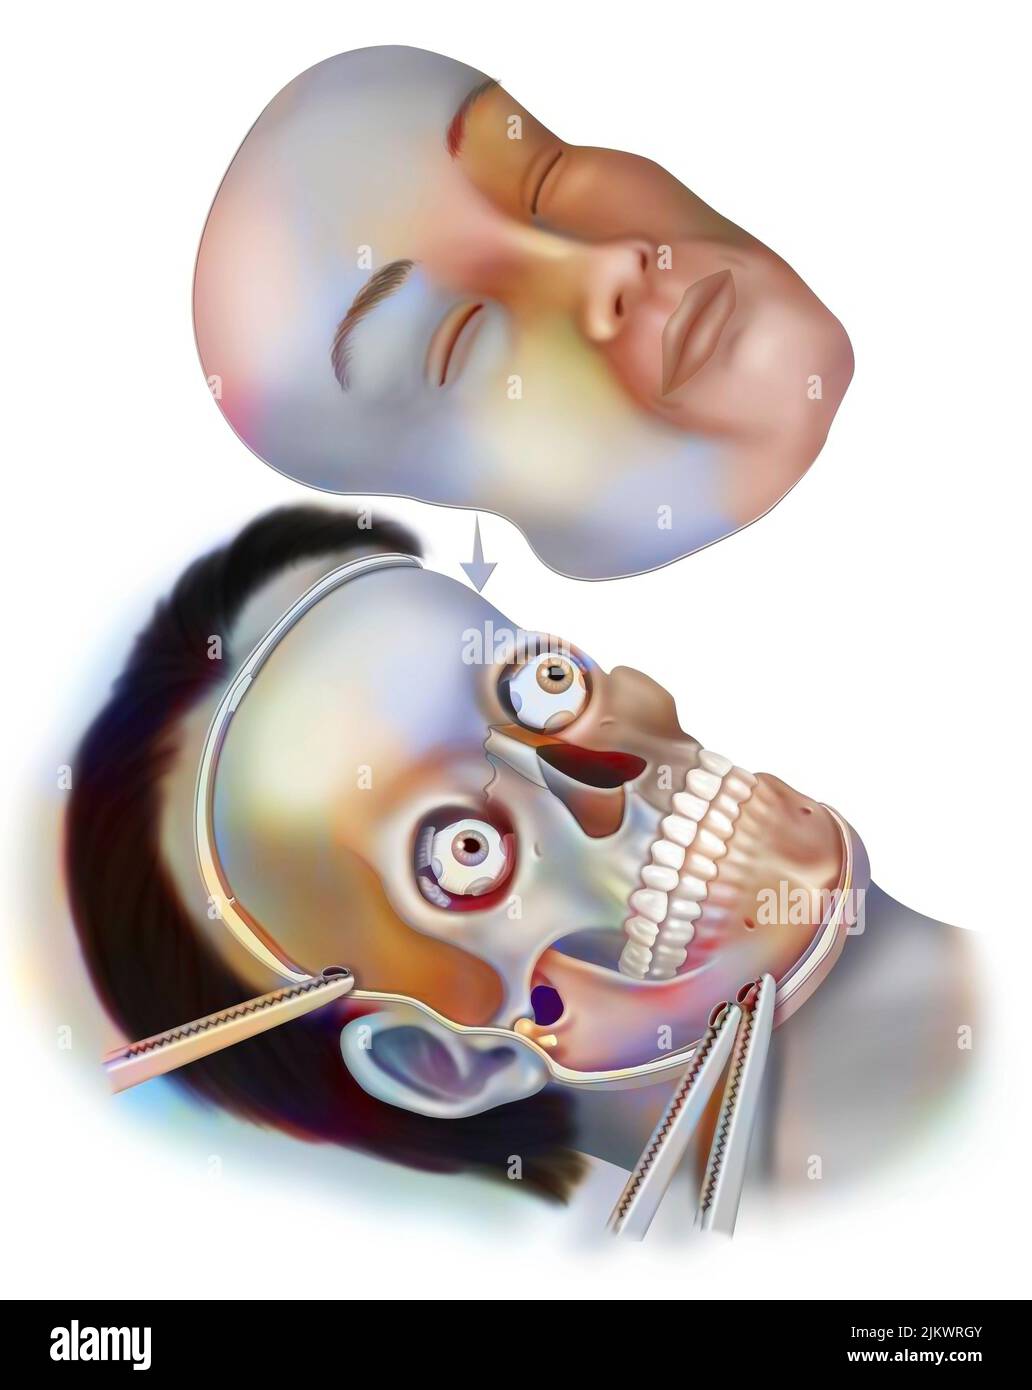

(4,132)Page 1 sur 42

Résultats de la recherche pour les photos et les images (4,132)

Page 1 sur 42